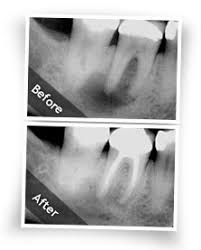

عرض معالجة جذور الأسنان(سحب العصب) !: اذا كنت تعاني من ألم في أحد أسنانك أثناء الأستلقاء أو أن الألم مستمر بدون سبب فهذا يعني أن التسوس قد أصاب عصب السن المصابة وهنا يلجأ الطبيب الى سحب عصب السن المصابة لأراحتك من هذا الألم . تخلص من ألم أسنانك الشديد المتواصل واحصل على خصم 40% لكل حالة سحب عصب

https://encrypted-tbn0.gstatic.com/i...434v0nZjsh2UL8 تمتعوا بشاهدة بعض الحالات التي تم علاجها لدينا ولاحظوا الفرق